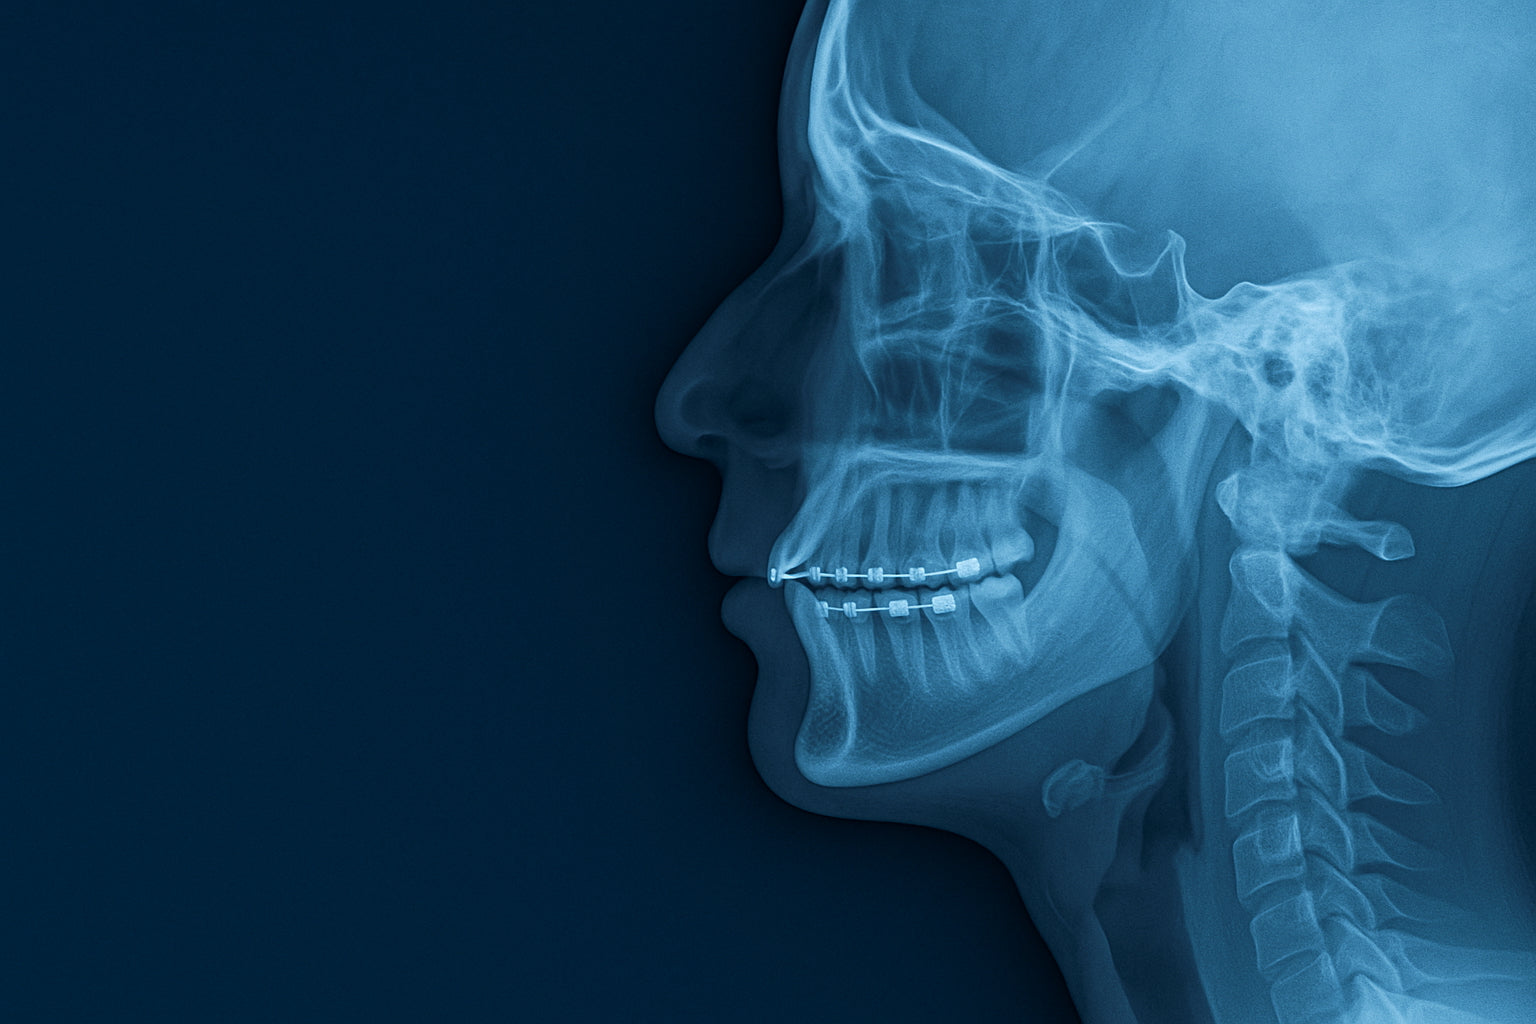

Et si votre mâchoire influençait votre posture, votre sommeil… et votre performance physique ?

L’orthodontie, on la croit souvent réservée à l’alignement esthétique des dents. Mais ce que peu de gens savent, c’est qu’un mauvais positionnement de la mâchoire peut perturber bien plus que votre sourire.

Un déséquilibre invisible, mais qui se propage

Lorsque vos dents ou votre mâchoire sont mal alignées, votre corps compense. Et cette compensation peut entraîner :

une posture déséquilibrée (tête poussée vers l’avant, épaules tendues),

des tensions chroniques dans le cou, les trapèzes ou le bas du dos,

des troubles de l’occlusion (quand les dents du haut et du bas ne s’emboîtent pas bien),

une respiration buccale au lieu d’un flux nasal sain.

L’orthodontie moderne n’est plus seulement cosmétique. Elle s’inscrit dans une vision fonctionnelle du corps, avec des impacts sur l’équilibre postural, musculaire et respiratoire.

Lorsque les arcades dentaires sont trop étroites, l’air circule mal, la langue repose en position basse, et le nez devient sous-utilisé. Ce déséquilibre peut remonter jusqu’aux muscles cervicaux et provoquer une hypercompensation posturale.